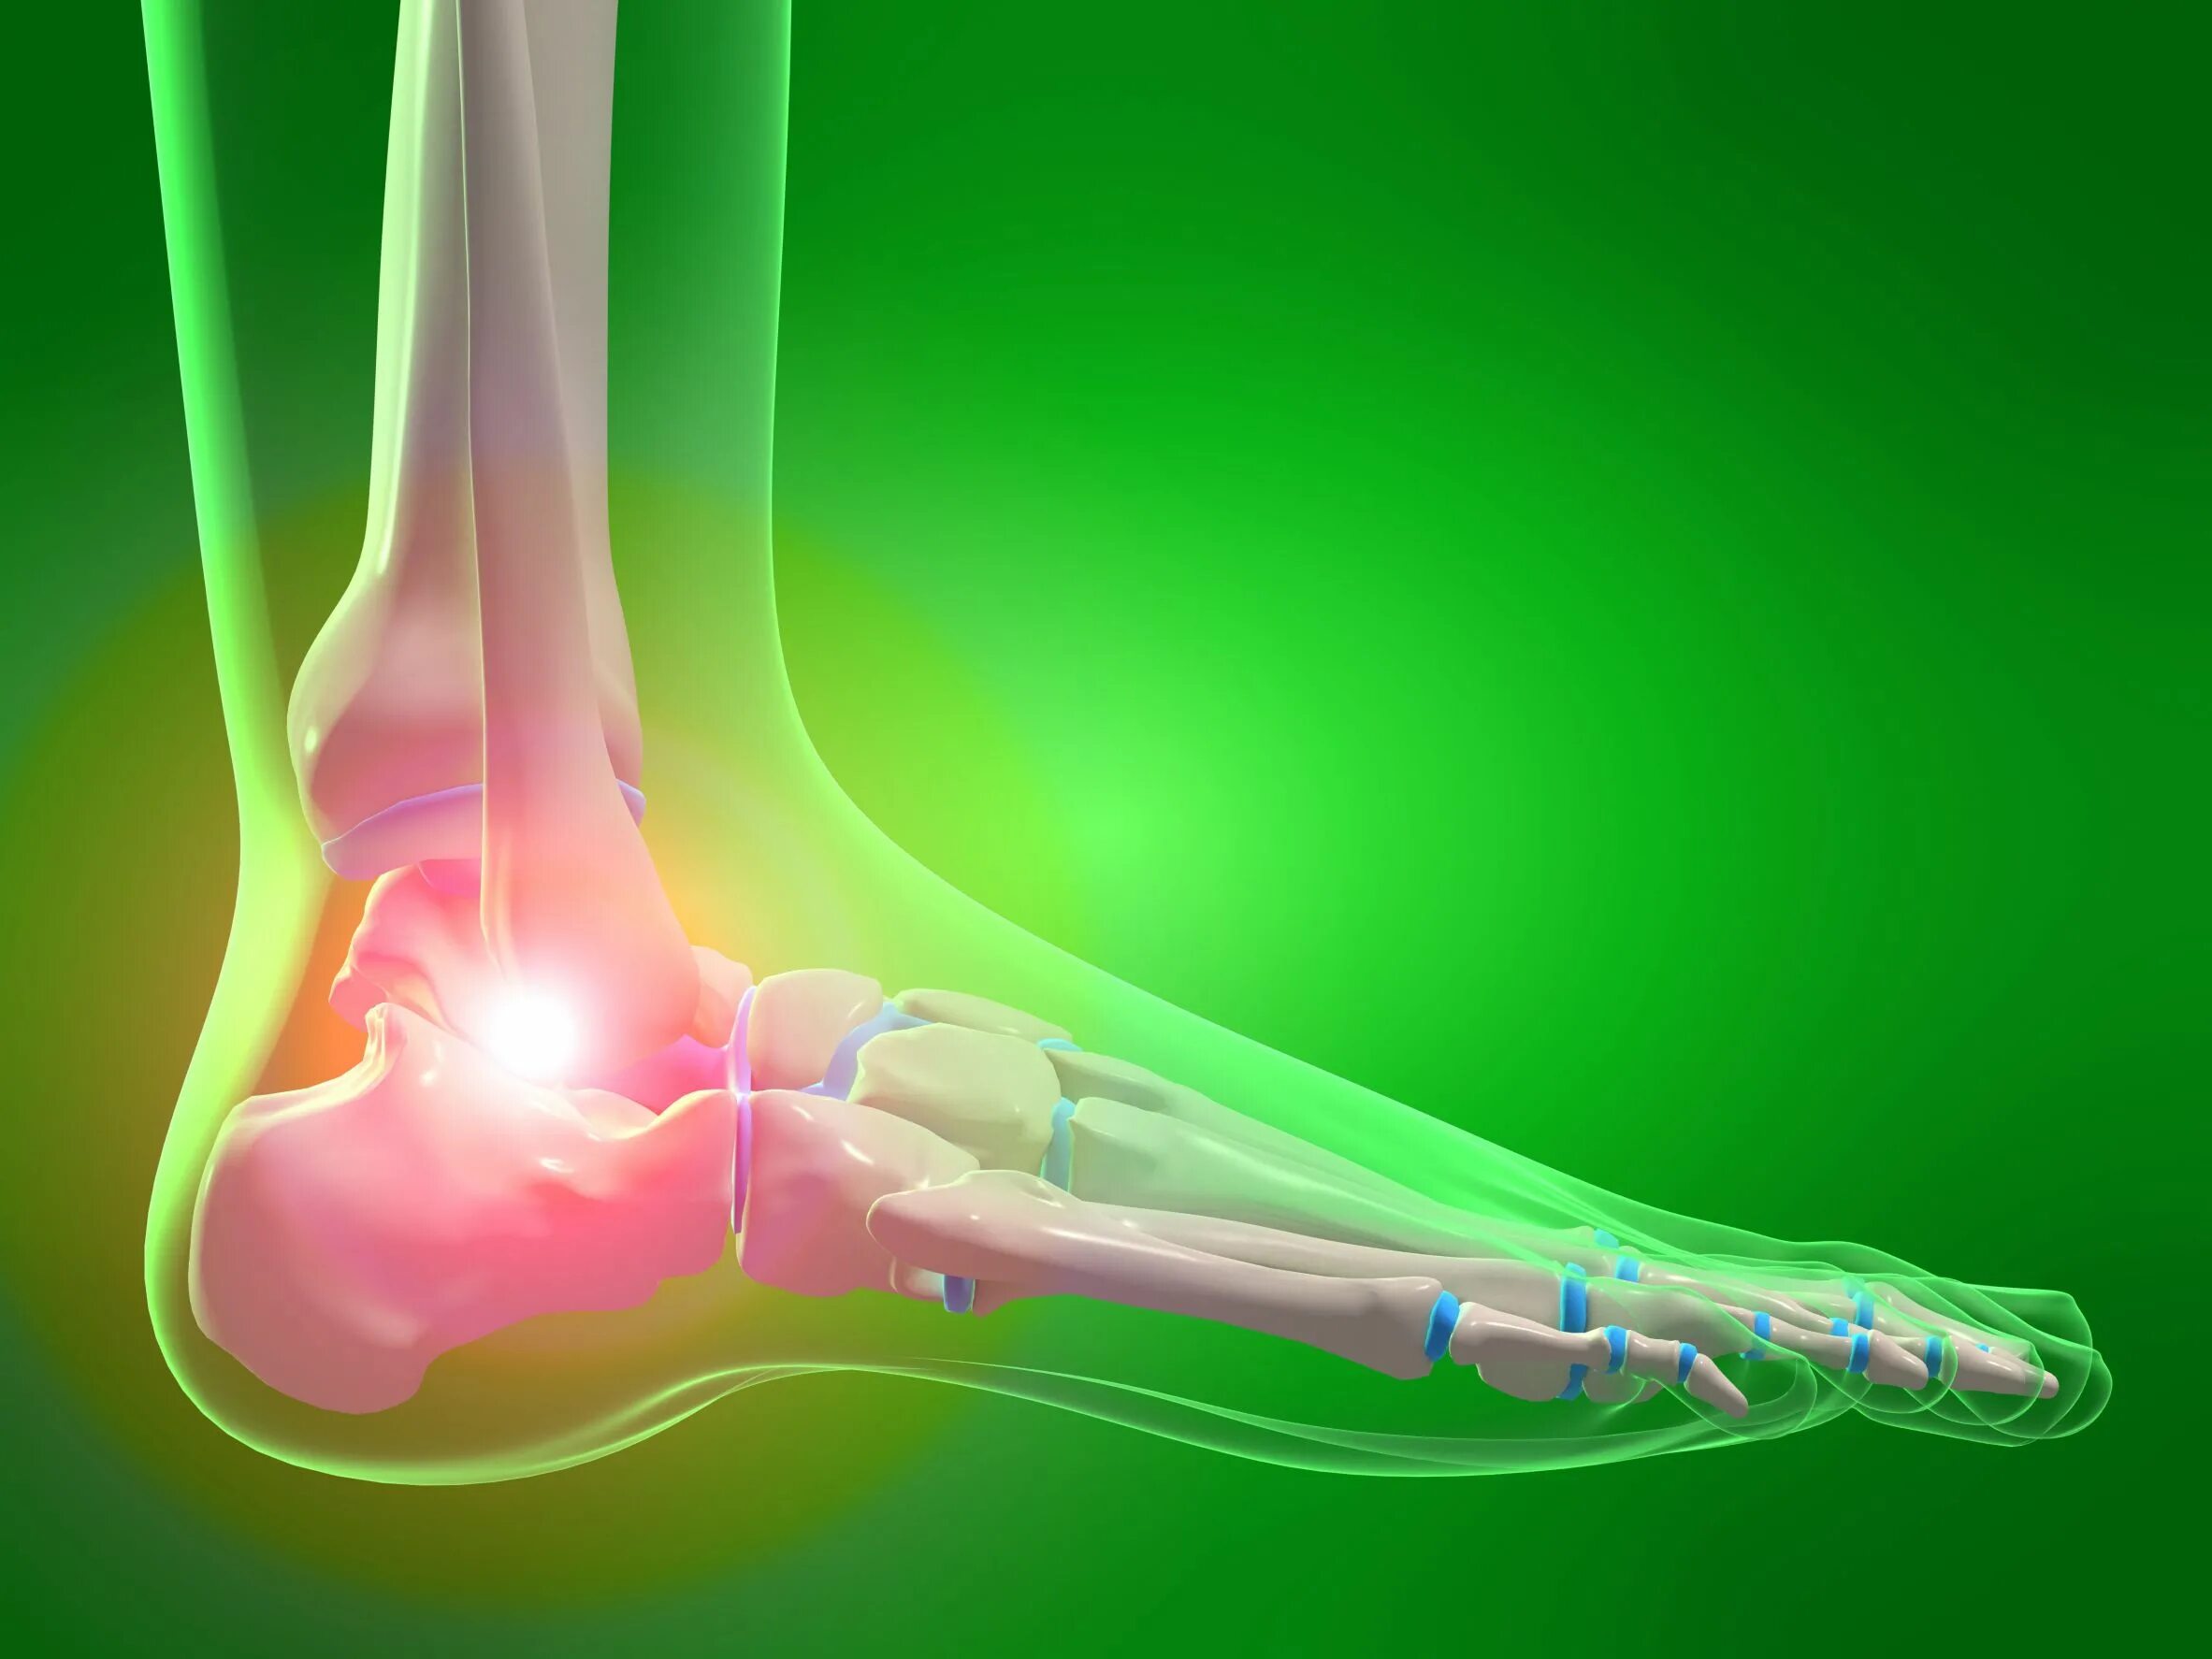

Артроз пяточных суставов